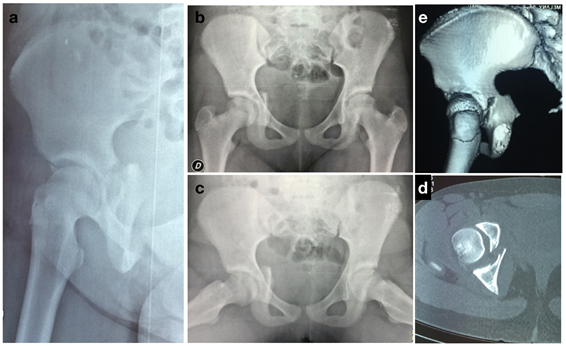

Se solicitan radiografías de frente de pelvis, enfoque de Lowenstein y el par de Judet. Se evidencia fractura del acetábulo derecho, involucrando el CTR. Se observa una disociación de la columna posterior a través del CTR, epifisiolisis tipo 1 de Salter y Harris. Se solicita una tomografía computada (TC) de pelvis que confirma desplazamiento articular ≥ 2mm, y clasificamos esta lesión como una tipo II de Bucholz5.

Se realiza una resonancia nuclear magnética (RMN) que descarta fragmentos osteocondrales intraarticulares así como lesiones del labrum cotiolideo.